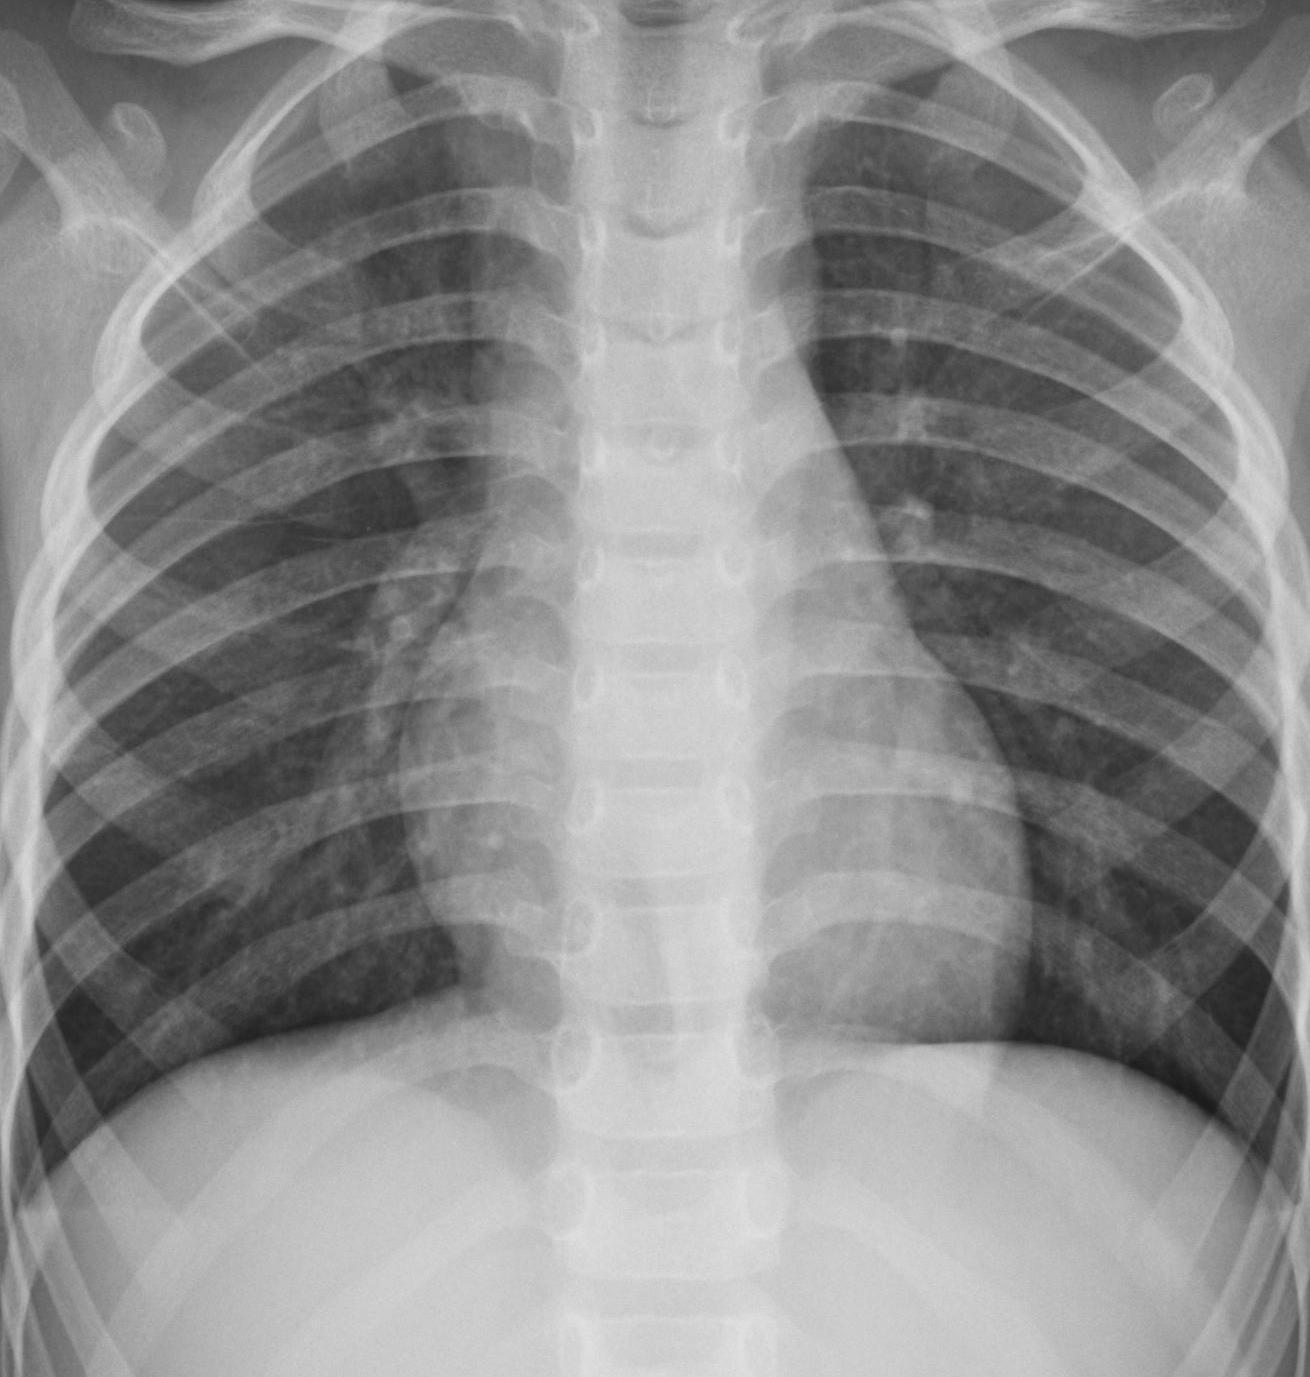

We conclude by presenting a methodological application of our estimation technique to the field of medical image analysis.

In [hogeweg2017fast], a method is presented for measuring symmetry in medical images, which offers a feature that improves disease detection. The first step involves determining an axis of symmetry. Subsequently, each point inside a shape on one side of the image (e.g., a point on the right lung) is compared to its symmetric counterpart in the shape on the other side of the image (i.e., the left lung). This comparison process results in a local symmetry measure. By averaging these local symmetry measures over the entire image, a global symmetry measure is obtained. This quantification helps in analyzing and detecting potential asymmetries or deviations from perfect symmetry in the medical images, which can be indicative of pathological changes or abnormalities. The combination of local and global symmetry measures provides valuable information for disease detection and medical image analysis.

Figure 6: (a) A frontal chest radiograph. The region of interest (the lungs) is highlighted. (b) A set of independent random points sampled uniformly from within the lung shape. The red line indicates the axis of symmetry estimated from this point cloud.

One issue here is that, despite existing protocols on medical imaging, in practice, the axis of symmetry is not known with certainty and must be estimated. The authors suggest estimating it as the direction that optimizes the proposed symmetry measure. In this matter, we will use our estimator to identify the axis of symmetry in a different way, which allows us to correctly align the images. By utilizing our estimator, we provide an alternative approach for estimating the axis of symmetry, contributing to improved medical image analysis and disease detection.

Refer to caption

Figure 7: Plot of the estimating function g^n\widehat{g}_{n} for the lungs data.

A way to compute our estimator is to draw a sample of random points inside the shapes that we are interested in analyzing. Suppose we have a grayscale image like the one shown in Figure 6(a), and we are interested in analyzing anomalies in the lungs. We can select pixels with a normalized intensity below a chosen threshold (here, 0.450.45, where 0 represents pure black and 1 pure white). We then draw a subsample of n=10000n=10000 points from these pixel locations with some added jitter, as shown in Figure 6(b).

By using this sampling procedure, we obtain a sample n={X1,,Xn}\aleph_{n}=\left\{X_{1},\dots,X_{n}\right\} from an unknown distribution FXF_{X} of X2X\in\mathbb{R}^{2} in the plane. If we assume that there exists a vector u𝕊1u\in\mathbb{S}^{1} that makes X=dRuXX\stackrel{{\scriptstyle d}}{{=}}R_{u}X, we would be able to estimate it consistently. It is important to note that this sampling procedure is intended solely for estimating the axis of symmetry, not for measuring the symmetry features that would require more information.

In Figure 7, the estimator g^n\widehat{g}_{n} is plotted. The figure clearly shows a unique global minimum in the direction of the angle close to π/2\pi/2, where the column is expected to be. The estimated axis of symmetry is displayed as the red line in Figure 6(b).